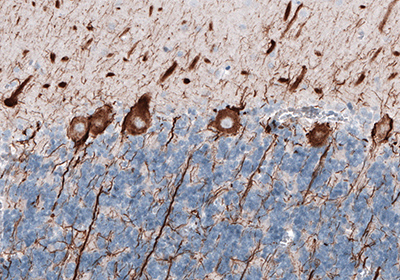

Representative Staining of Neurofilament Using Monoclonal Anti-NEFL Antibody (AMAb91314)

Figure 1. The human cerebellum shows strong cytoplasmic immunoreactivity in cell bodies and proximal dendrites of Purkinje cells.